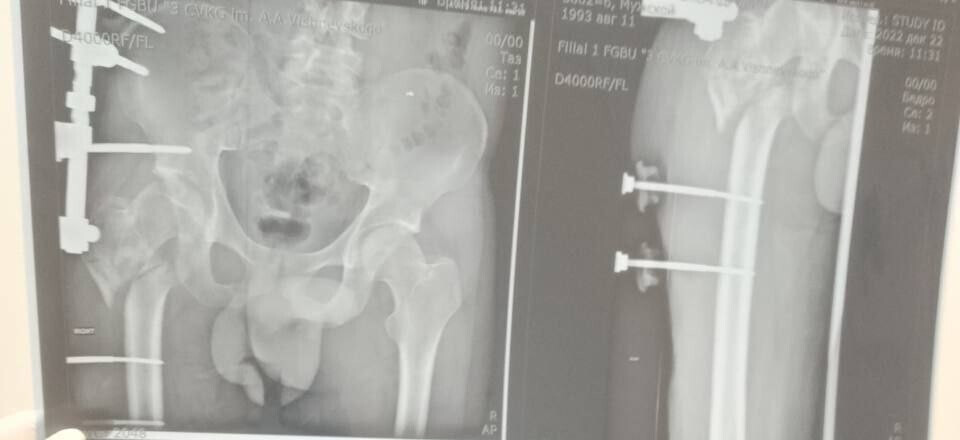

Руководитель Минздрава рассказала, что борьба с травмой сержанта из ЛНР длилась три с половиной года. За это время он проходил лечение в десяти госпиталях, в том числе в Москве и Санкт-Петербурге. В июле 2024 года военнослужащий, удостоенный медали «За отвагу», был уволен со службы по состоянию здоровья. Из-за обширных повреждений и многократных операций правая нога бойца стала короче левой на восемь-девять сантиметров. Обычное эндопротезирование изменить ситуацию не могло.

«Вместо стандартной замены сустава пациенту выполнили сложнейшее вмешательство с использованием ревизионных систем эндопротезирования, в ЛНР такую операцию провели впервые», — цитирует Пащенко ЛИЦ.

Она уточнила, что главная задача хирургов заключалась не просто в установке импланта, а в восстановлении биологической оси конечности и компенсации укорочения.